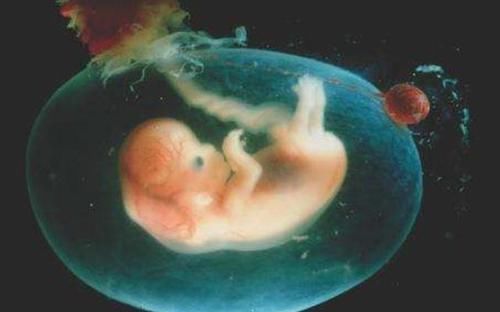

而这层保护罩其实就是羊膜,它可以起到保护小婴儿的作用。

羊膜具体有哪些作用?1、帮助宝宝呼吸

我们可以把羊膜比喻成摇篮,胎宝宝被羊膜包裹就像在摇篮中发育一样,而羊膜可以使宝宝周围的温度保持恒温,可以保证更多的氧气能帮助宝宝更好的呼吸。如果宝宝带着羊膜出生,那么便能更快地接受外界环境。

2、保护胎儿

婴儿被羊膜包裹其实就相当于多了一个保护层,一旦羊膜破了,那么羊水就会流出。相信怀孕过的女性都知道,一旦羊水破了其实是很严重的,轻则会导致流产,因此它的另外一个作用就是为了保护胎儿。

3、避免宝宝被压迫

当宝宝还没有出生,在妈妈子宫中发育的时候,宝妈的一些行为也会影响到宝宝,比如妈妈快速的走路或者突然坐下,胎儿都能感受到震动。而羊膜就可以缓解症状,避免小孩被压迫。